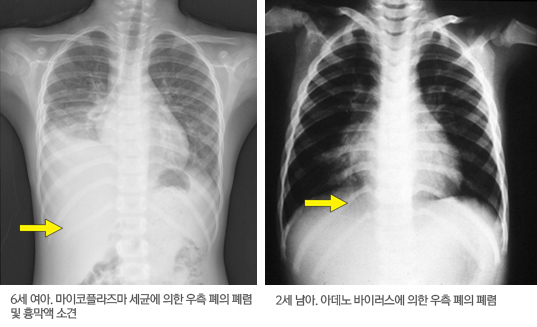

폐렴의 진단은 일반적으로 병력 청취, 진찰과 흉부 방사선 소견 등을 통해서 가능하다. 하지만 폐렴 초기에는 청진이나 방사선 소견은 정상일 수도 있으므로 발열 및 기침 등의 증상이 지속될 시에는 추적관찰이 필요하다. 폐렴을 시사하는 진찰 소견으로는 청진상 폐음이 감소되어 있거나 나음이나 천명 같은 이상 소견이 있을 때, 폐의 염증이 심해져 물이나 농이 찼을 때이며 이런 시기에 타진하면 이상 소견을 보일 수 있다. 1. 단순 흉부 방사선 검사: 폐렴 단순 흉부 방사선 사진상 다양한 양상의 음영 증가 소견이 관찰된다. 바이러스 폐렴은 폐가 과도하게 팽창되어 늘어나 있거나 양쪽 폐의 음영이 증가되어 있을 때가 많다. 세균성 폐렴은 폐의 대엽성 또는 소엽성 침윤을 보이기도 하나 이러한 방사선학적 소견만으로 폐렴의 원인을 구분할 수는 없으며 임상적 소견이 바탕이 되어야 한다. 2. 혈액 검사: 혈액 검사를 시행하면, 백혈구나 혈침 속도, C-반응 단백질 같은 염증을 나타내는 지표가 상승되어 있는 결과를 보일 때가 많다. 그러나 특히 바이러스성 폐렴은 혈액 검사가 정상 소견을 보일 수도 있기 때문에 혈액 검사만으로 폐렴을 진단할 수는 없다. 세균성 폐렴에서도 피에서 균이 발견되는 것은 극히 일부이므로 원인균을 밝혀내는 것이 쉽지 않다. 마이코플라스마나 A군 연쇄상구균 폐렴은 혈액 검사로 항체가를 측정하여 진단을 한다. 3. 호흡기 검체 검사: 호흡기 검체는 가래나 코 분비물을 이용한 검사이다. 소아는 가래를 자발적으로 배출할 수 없기 때문에 대부분 코의 분비물을 채취하여 바이러스 검사를 시행한다. 검사 기법의 발전으로 현재는 호흡기 분비물에서 바이러스를 신속하게 검출할 수 있다. 그러나 세균의 경우 많은 소아들은 증상을 보이지 않는, 코와 인후부에 다양한 종류의 상재균을 가지고 있기 때문에 콧물 검사로 폐렴의 원인이 되는 세균을 확인하기는 어려울 때도 있다. 4. 폐조직 생검: 폐렴의 원인 확인을 위하여 마취를 한 후 수술적으로 폐의 일부 조직을 얻는 검사법으로 대부분의 폐렴의 경우에는 시행하지 않으나, 심한 폐렴 및 면역저하환자에서 발생한 폐렴 등의 일부 경우 의료진의 판단 하에 시행할 수 있다. 5. 그 외의 검사: 폐에 물이나 농이 찼다면 CT(컴퓨터단층촬영), 초음파로 병변을 확인하기도 하며 필요 시에는 물이나 농을 빼주는 시술도 시행하게 된다.